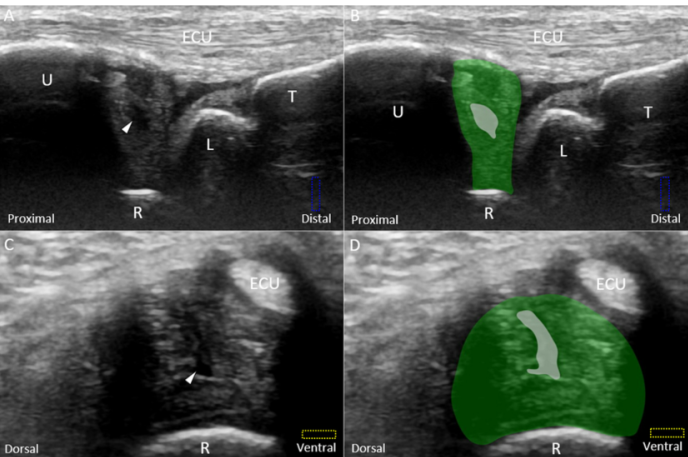

민트색 박스 표시한

척골 경상돌기(Sp)에 프로브를 대고

TFCC 장축 스캔을 하면요.

가장 바깥에

척측수근신근 힘줄이 보이고요.**

(ECU, extensor carpi ulnaris)

잘 보이시진 않겠지만

힘줄집(subsheath)을

신전근 지대(Extensor retinaculum)가

감싸고 있는 형태입니다.

그 아래에 파란색으로 표시한

척골 측부인대(Ulnar collateral ligament)

가 보입니다.

그 아래는 빨간색으로 표시한

반월 연골 유사체(Meniscus homologue)

가 보이고요.

그 아래는 귤색으로 표시한

요척 인대(Radio-Ulnar ligament)

얕은층(superior limb)와

깊은층(deep limb)으로 보입니다.

반월 연골 유사체 아래에는

보라색으로 표시한

월상 삼각 인대(Luno-Triquertral ligament)

그 아래에는 녹색으로 표시한

가장 중요한 구조물이죠.

바로 '삼각섬유연골' 이라는(Triangular fibrocartilage, TFC)

관절 디스크(Articular disc)가

요골에 붙어있습니다.